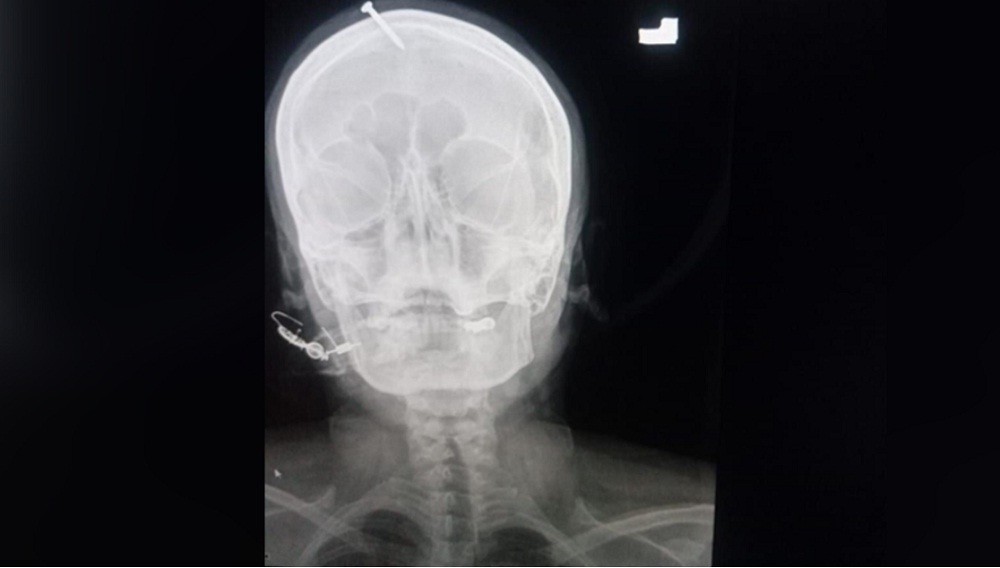

Foto sinar X kepala ibu hamil yang ditancapkan paku oleh dukun di Pakistan. (Foto: Twitter)

Foto sinar X menunjukkan, paku sepanjang 5 cm telah menembus bagian atas dahi perempuan itu, tetapi tidak mengenai otaknya. Khan mengatakan, paku itu tampaknya ditancapkan ke kepala sang ibu dengan palu atau benda berat lainnya.